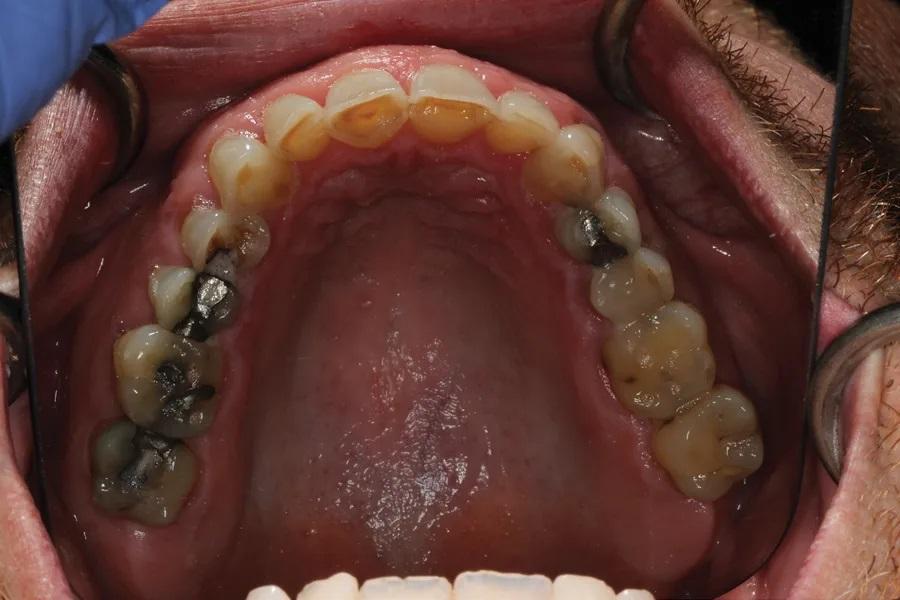

Биомеханика: Кариозные поражения: 1.6–1.3, 2.4, 2.5, 3.7, 3.5, 3.4, 4.4. Крупные реставрации: 1.7–1.3, 2.5–2.7, 3.7–3.5, 4.5, 4.6. Три зуба под коронками; эндодонтическое лечение ранее — 3.6 и 3.5. Зуб 3.7 — значительная утрата тканей. На передних зубах — умеренно-тяжелая атриция и эрозия. Ряд реставраций на 1.4, 2.3, 2.4, 3.7 — неудовлетворительное состояние/неудачные (Фото 5 и Фото 6).

Фото 5. Окклюзионный вид верхнечелюстной дуги до лечения. Обратите внимание на большие реставрации, истирание и эрозию.